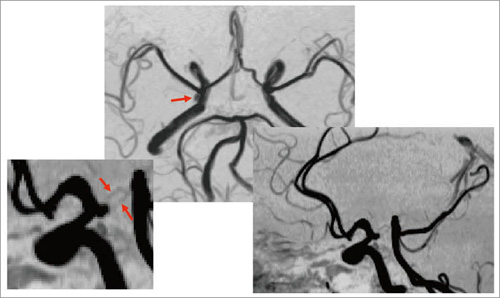

図4 3D TOF(脳動脈瘤)

頭部MRAの撮像法を表1-(2)に,画像を図3に示す。3D TOFは,MTCパルスを付加することにより,末梢までの血管が明瞭に描出できる。また,3-slabで撮像するが,slabとslabの間は信号差がほとんど目立たず,まるで1-slabで撮像したかのように見える。図4の症例では,瘤から出ている細かい血管まで,はっきりと描出されているのがわかる。